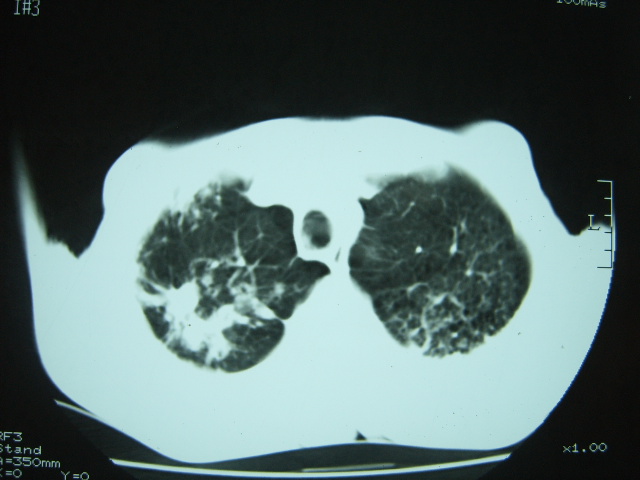

男74岁,咳嗽,寒战,低烧。有糖尿病史。

两肺结核,空洞形成,左下肺肺段隔离症待排

两肺慢性炎症伴脓肿形成,不除外继发霉菌感染。

1、左下肺肺脓肿,合并霉菌球形成?.2、双肺陈旧性病灶.3、右上肺病灶警惕瘢痕癌,建议定期复查.

两肺结核,左下肺空洞性病变,结核性?炎性?癌性?抗炎治疗后复查。

两肺结核,左下肺大片实变,内见空洞性病变,壁不规则,结合糖尿病史,考虑:结核性?霉菌性?建议结合实验室检查或治疗后复查。